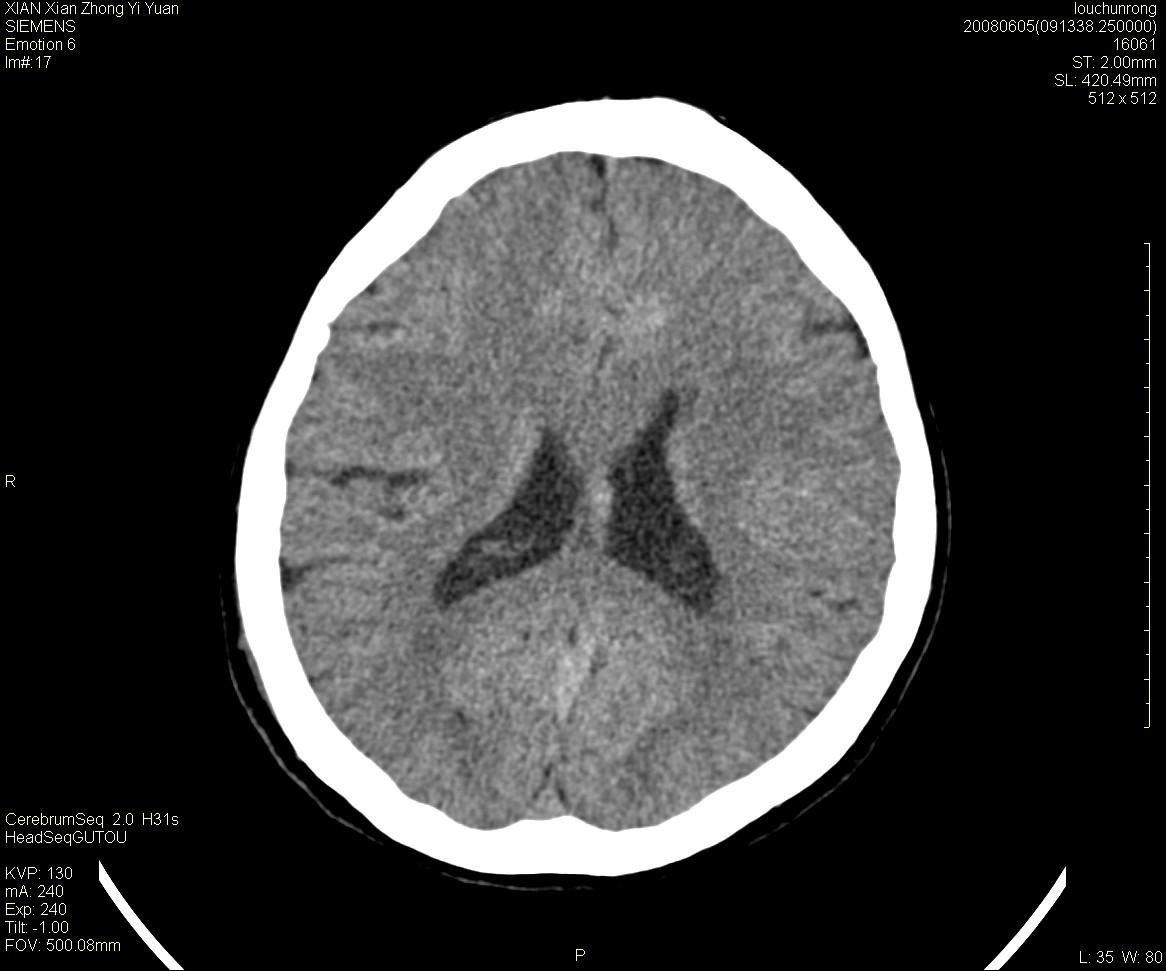

标题: CT13860:F52Y,,头外伤致头晕半天,以前无不适。 [打印本页]

标题: CT13860:F52Y,,头外伤致头晕半天,以前无不适。

层厚2mm。

左侧侧室内血管异常增粗,考虑血管变异或血管瘤可能,余未见异常

大家看左额叶大脑镰旁高密度影

两侧脑室体部距离增宽,胼胝体发育不良?

中线附近、枕叶近枕骨处及脑内多发点条状强化影,考虑血管异常?

大脑大静脉池内的密度不均,双侧脑室增宽,我看右异常这块。战友们看看

侧脑室前角变形、变窄,考虑侧脑室粘合;余未见明显异常。